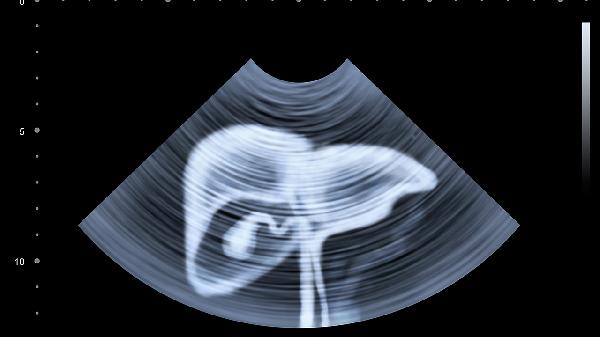

这些信号可能比体检指标更早出现!有位患者就是发现小便持续发黄两周后,检查出早期肝硬化。现在起每次如厕后花10秒钟观察一下,相当于给肝脏做免费体检。如果发现上述任何异常持续超过3天,建议尽快做肝功能检查和腹部B超。记住,肝脏的求.救信号很隐蔽,但只要我们足够细心,完全可以在关键时刻拉它一把!